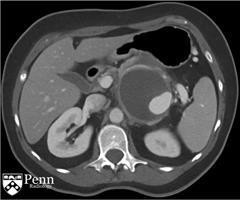

马女士, 55岁,左腰痛。腹部增强CT如下图所示。

于胰体/尾部的巨大的分叶状的囊性肿块,包绕脾动脉。其内可见一致密物在病变的内部下方与其分层。脾静脉内形成血栓,导致明显的胃肝和胃脾静脉曲张。见一假性动脉瘤起源于脾静脉的分支。

诊断:粘液性囊性肿瘤伴低度不典型增生,仅局限于胰腺,邻近慢性胰腺炎和假性囊肿形成伴囊内血栓。